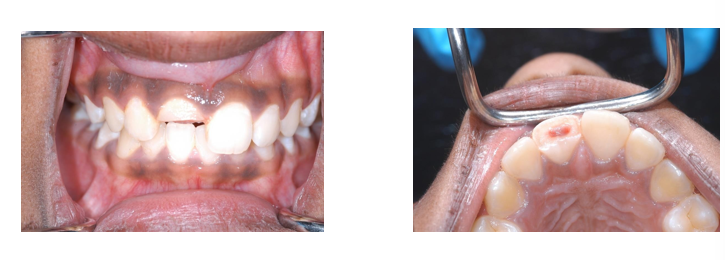

What procedure does this child require?

Partial pulpotomy